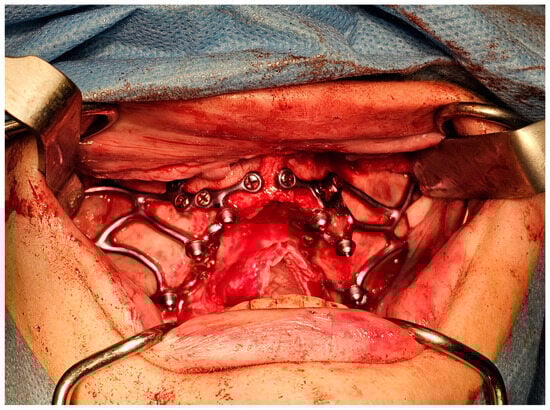

2.5.2. Zygomatic Implants

Surgical Technique